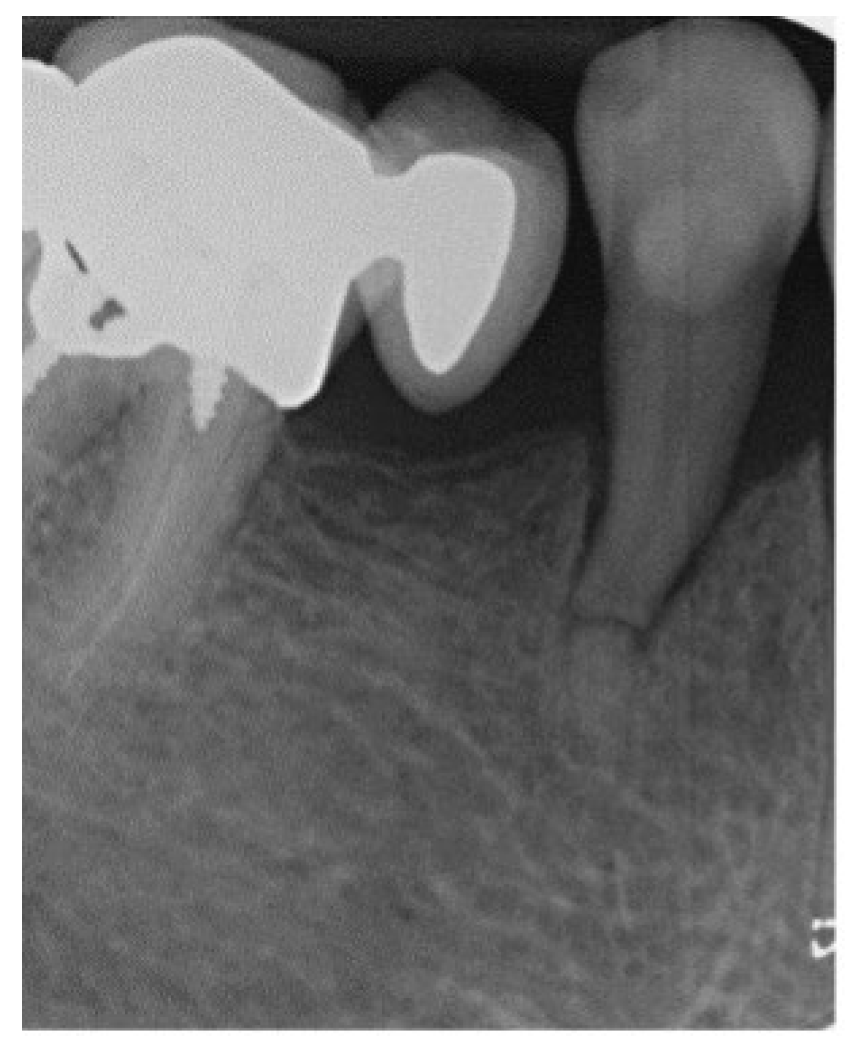

4. Subgingival Fractures

- B. Supracrestal Infra-attachment level fracture (SIAL)

4.3. Treatment

4.4. Follow-Up